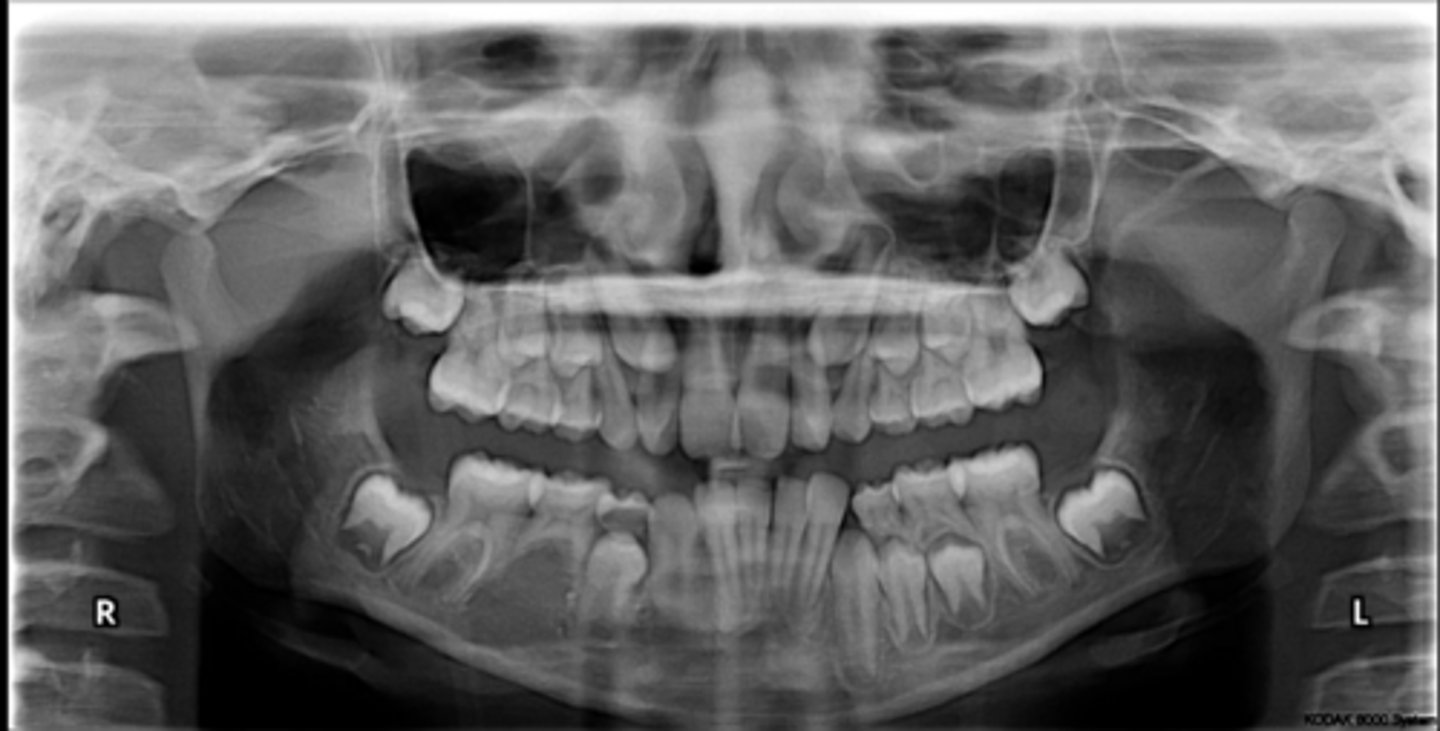

Yes - #2, also #27?

Dilacerated roots?

No

Are there congenitally missing teeth in the maxillary arch?

Are there congentially missing teeth in the mandibular arch?

Any supernumerary teeth?

Yes - mandibular second molars

Any impacted teeth?

Yes

Are the condyles symmetrical?

Maybe in the upper molars

Are there any dilacerated roots?

Are there congenitally missing teeth in the mandibular arch?

Are there any supernumerary teeth?

Are there retained primary teeth?

A little bit

Is there crowding?

Is there any pathology?

Possibly #20